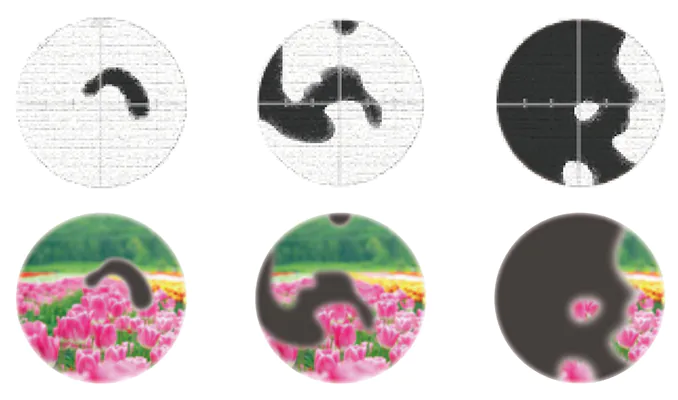

国内で行われた疫学調査で40歳以上の20人に1人が緑内障という結果が報告されています。緑内障は日本人の中途失明原因疾患の第1位であり、見える範囲である視野が狭くなる病気です。緑内障で失われた視野を取り戻すことは不可能であり、進行を止める治療しかできないことから、「見る力」を保つためには早期発見と治療の継続が非常に重要です。

- 見える範囲が狭くなった

- 片目では見えない部分がある

視神経乳頭陥凹拡大や

緑内障の疑い

網膜からの視覚情報を脳へ送る視神経乳頭の中心には少しへこんだ陥凹部がありますが、緑内障ではこのへこみが拡大します。緑内障は進行を抑制する治療は可能ですが、失われた視野は取り戻せないので、視神経乳頭陥凹拡大や緑内障の疑いを指摘された場合には、できるだけ早くご相談下さい。

網膜からの視覚情報を脳へ送る視神経乳頭の中心には少しへこんだ陥凹部がありますが、緑内障ではこのへこみが拡大します。緑内障は進行を抑制する治療は可能ですが、失われた視野は取り戻せないので、視神経乳頭陥凹拡大や緑内障の疑いを指摘された場合には、できるだけ早くご相談下さい。